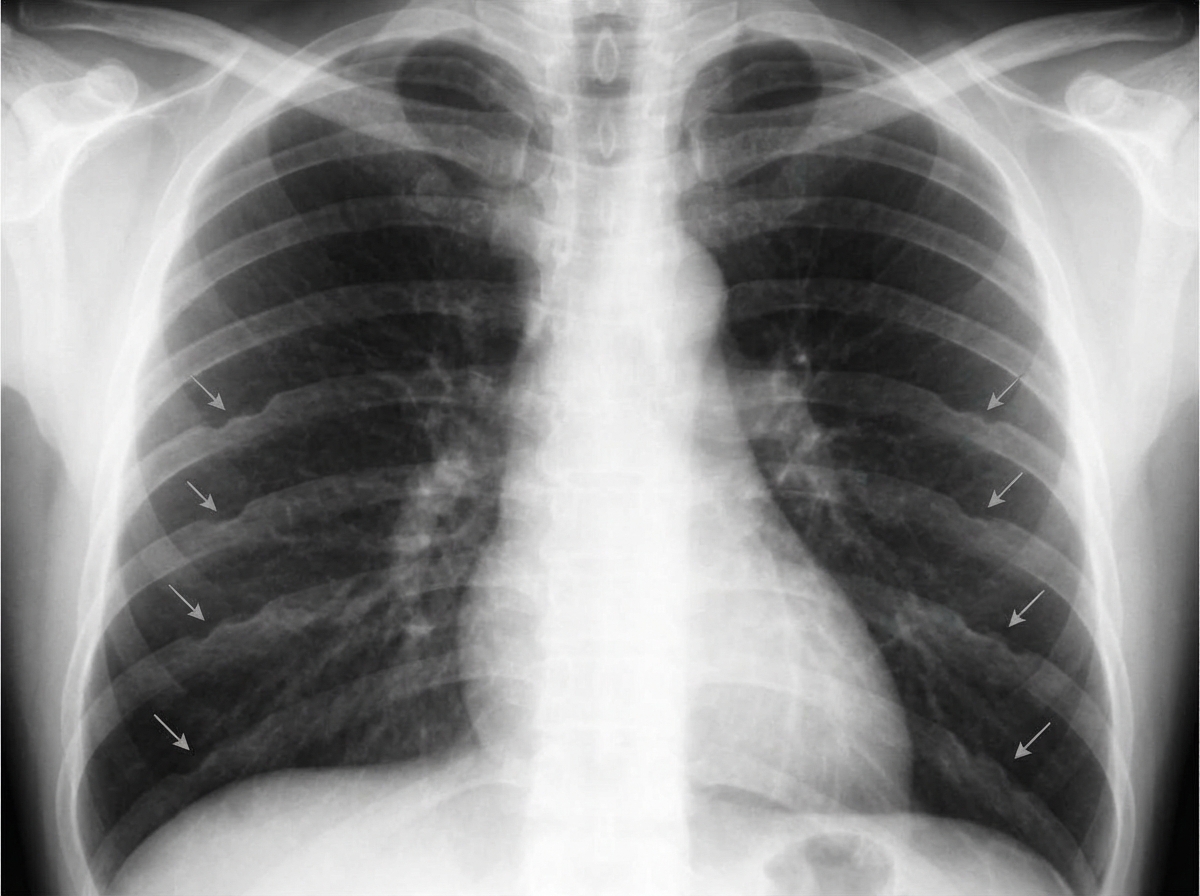

In the condition shown below, rib notching is present in which of the following ribs? (AIIMS Nov 2015)

Explanation: **3rd to 9th ribs** - The image provided depicts **coarctation of the aorta**, characterized by a narrowing of the aorta, typically distal to the origin of the left subclavian artery. - In coarctation of the aorta, collateral circulation develops through the **intercostal arteries** to bypass the constriction, leading to their enlargement and subsequent erosion of the inferior margins of the **3rd to 9th ribs**, a finding known as "rib notching." *1st to 9th ribs* - While rib notching affects upper ribs, it typically **spares the 1st and 2nd ribs** because the superior intercostal arteries (which supply these ribs) originate directly from the subclavian artery, often proximal to the coarctation, so they do not participate in collateral circulation as significantly. - The pattern of notching is usually more concentrated in the mid-thoracic region. *11th and 12th ribs* - Rib notching from coarctation of the aorta is rarely observed in the **floating ribs** (11th and 12th ribs). - These ribs have a different anatomical relationship with the pleura and typically do not bear the brunt of increased collateral flow from the intercostal arteries in the same way as the higher ribs. *All ribs* - Rib notching is a localized phenomenon reflecting increased blood flow through specific intercostal arteries involved in collateral circulation due to aortic coarctation. - Therefore, it does **not affect all ribs**, and its absence in certain ribs (like the 1st, 2nd, 11th, and 12th) helps differentiate this condition radiologically.